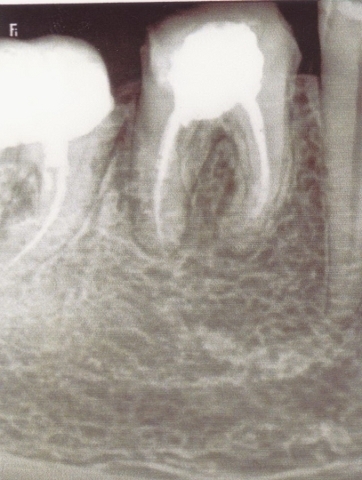

Примеры лечения радикулярных кист челюстей без скальпеля:

Фото: до лечения депофорезом

Фото: после лечения депофорезом